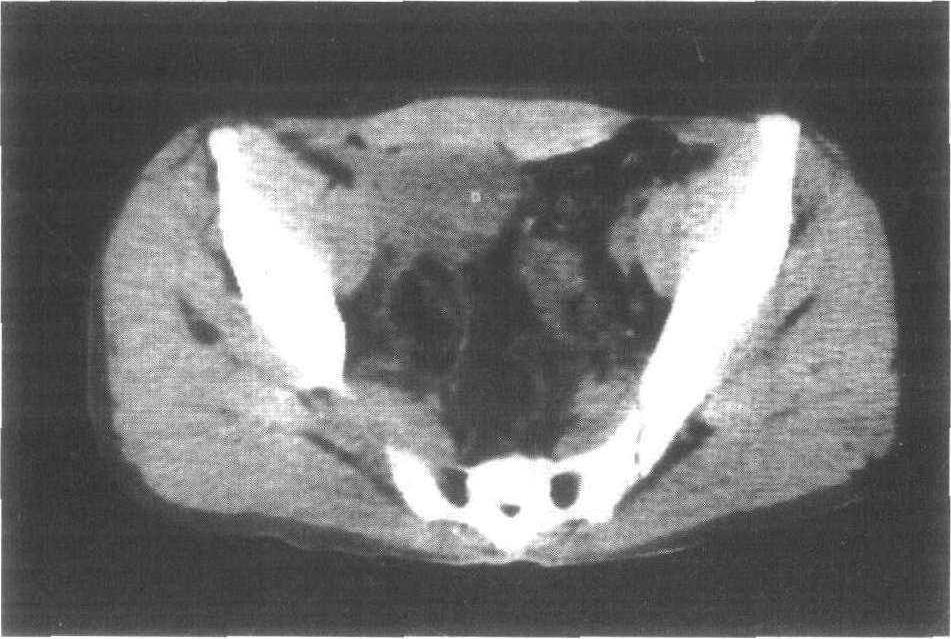

好在功夫不负有心人,几天几夜的查询后,答案大白于天下。“张大勇得的,是猫叫综合征,这是一种染色体疾病。”

猫叫综合征,1963年,由遗传学家Jerome Lejeune提出。根据研究,缺失的染色体一般源于父亲的精子。

遗憾的是,目前并没有彻底治愈这种疾病的方法。